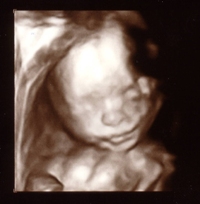

Here is mine. I love it!

See that's what i'm talking about! That's a good one compared to mine!

Thank you. He actually looks exactly like my DS' at 20 weeks. It's scary!